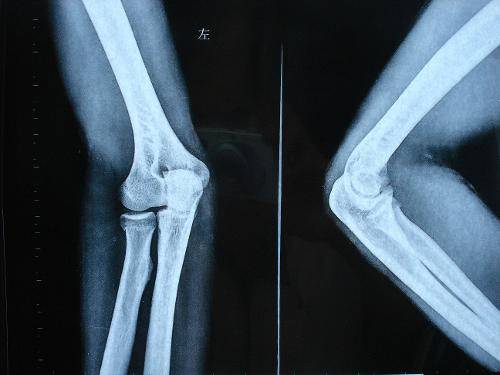

康复训练的后期已达到临床愈合或已经去除外固定,此时骨性骨痂已形成,X线检查已显影,骨骼有了一定的支撑力,但大多存在邻近关节的关节活动度下降、肌肉萎缩等功能障碍。此期康复的目的是恢复受累关节的关节活动度、增强肌肉的力量,使肢体功能恢复。康复训练主要形式是伤肢关节的主动活动和负重练习,使各关节迅速恢复到正常活动范围和肢体的正常力量。恢复期进行康复的同时可配合理疗及步态训练等。